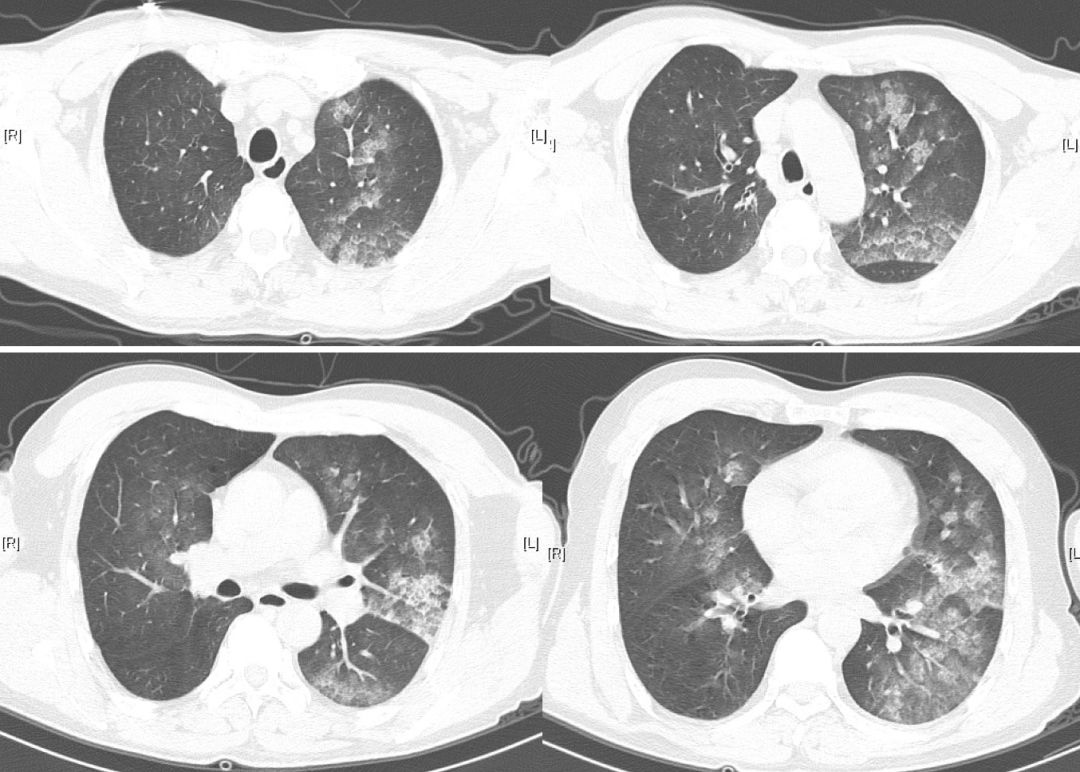

【图2】接触三氯甲烷当天胸部HRCT

双肺多发斑片状渗出灶,呈向心分布,左肺为著,符合肺水肿。